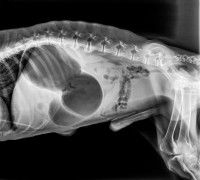

Pour des raisons encore mal connues, il arrive que l’estomac d'un chien se dilate de manière anormale. Cela se produit le plus souvent à la suite d'une accumulation de gaz, de liquides et/ou de solides (généralement ingurgités à l'occasion d'un repas), accompagnée d'un dysfonctionnement plus ou moins marqué du phénomène naturel de vidange du contenu de l'estomac vers les intestins. Ce dernier se met alors soudainement à gonfler, jusqu’à occuper parfois plus de la moitié de l’abdomen.

Même si ce n'est pas systématique, l'augmentation anormale de volume conduit le plus souvent à une torsion de l'estomac. Ce dernier se retourne sur son axe principal (un peu comme un hamac), la plupart du temps dans le sens des aiguilles d'une montre. Ce retournement gêne encore plus - voire bloque totalement - la vidange de l'estomac vers les intestins, ce qui accroît encore la dilatation. Autrement dit, un véritable cercle vicieux se met en place.

À cause de ce phénomène, les autres organes présents dans le thorax et l'abdomen sont comprimés, tout comme la veine porte et la veine cave caudale, qui sont chargées de ramener le sang vers le coeur depuis la rate, les reins et les membres postérieurs. Cela provoque une mauvaise oxygénation de ces organes, une baisse de la tension artérielle, et in fine un état de choc pouvant être fatal. D'après une étude intitulée « Canine gastric dilatation/volvulus syndrome in a veterinary critical care unit: 295 cases (1986-1992) » et publiée en 1995 dans le Journal of the Americain Veterinary Medical Association, le taux de létalité avoisinerait les 30% : autrement dit, en moyenne près d'un chien touché sur trois en décéderait.